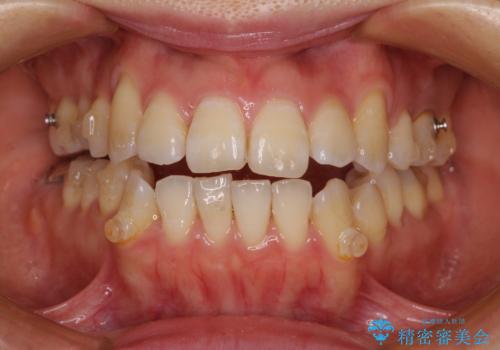

八重歯と開咬の抜歯矯正 ワイヤー装置を併用したインビザライン矯正治療

- 咬み合わない前歯と八重歯などのデコボコを気にして来院された患者様です。

上下前歯の位置を比較すると上顎が前方にあり、デコボコ改善でより上顎が前方に行く可能性があります。

開咬の改善にはインビザラインが有効であり、インビザライン単体での治療を検討しましたが、上顎前突を回避するために上顎左側第一小臼歯抜歯を行うこととしたため、補助装置とワイヤー矯正を併用した上で、インビザラインによる矯正治療を行うこととしました。